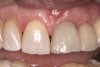

Following the successful integration of implants in the esthetic zone and creation of satisfactory hard- and soft-tissue volume, the restoring clinician is responsible for managing and shaping the definitive soft-tissue architecture. In the esthetic zone, this is a process generally achieved through the use of an implant-retained provisional restoration. The restoring clinician and technician should be intimately familiar with esthetic principles of tooth size, shape, and position. However, the subgingival area of the provisional restoration is also vitally critical. This area, known as the “emergence profile” (Figure 1), plays a significant role in the creation and maintenance of a satisfactory gingival architecture and will ultimately determine the final architecture of the peri-implant soft tissue.

The final architecture of the soft tissue is ultimately a result of the foundation of bone and soft tissue and the shaping and support of these tissues by the prostheses.16 In the esthetic zone, far too much uncertainty is brought about when the clinician moves from healing abutments to definitive prostheses without utilizing an implant-retained provisional restoration.17 This procedure can be used in both immediate and delayed loading approaches. The provisional restoration allows maturation and development of the peri-implant tissues in a form resembling the desired final outcome. The emergence profile can also be modified as needed to reposition the peri-implant soft tissue. Use of the provisional restoration in this manner creates an exceptionally predictable protocol whereby the clinician, patient, and all other involved parties can evaluate the final outcome before the definitive prostheses are even fabricated.

Following sufficient time for osseointegration and maturation of the soft tissue, the peri-implant architecture can be evaluated. Because the initial emergence profile was quite narrow, there may be an excess of soft tissue (which is rather desirable around an implant) (Figure 14). The mesio-distal width of the tooth may also be deficient at the gingival aspect. At this time, the restoration is removed and the deficient areas are augmented with composite or acrylic. Open gingival embrasures should also be closed, if desired. When the restoration is reinserted onto the implant the tissue will blanch, indicating that the increased emergence volume is placing pressure and reducing blood flow. The tissue will migrate away from this pressure, but it is unknown how far and how quickly this will occur.

Clinicians cannot fully predict how peri-implant tissues will respond to treatment and modifications, nor can they completely understand what the patient is expecting. Use of a provisional restoration and careful manipulation of the emergence profile provides in-situ testing of the patient’s biology, adaptation, and expectations. Changes to the position of the soft tissue can be tested, proven, and modified as needed and to the extent possible given inherent patient factors. When all of the parties involved are satisfied with the results in the provisional, the final impression is made (preferably with customized copings) and the technician will now have a comprehensive blueprint to follow.

Fig 17. Creation of the final soft-tissue architecture during the provisional stage provides a superior level of predictability and will minimize the chance of tissue changes following placement of the definitive restoration.